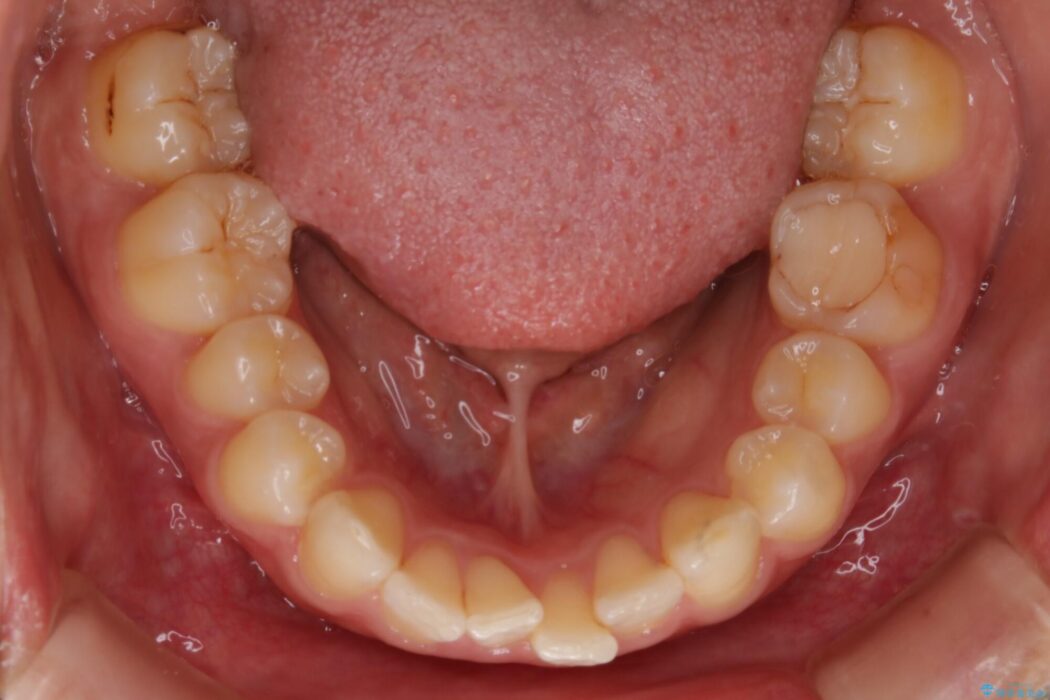

下顎前歯のガタつきを気にされて来院されました。

狭窄歯列とは幅が狭くなっている歯並びのことです。

本症例では下顎の歯列が舌側へ傾くことにより幅が狭まっていましたので、マウスピース治療により歯列弓を拡大しました。